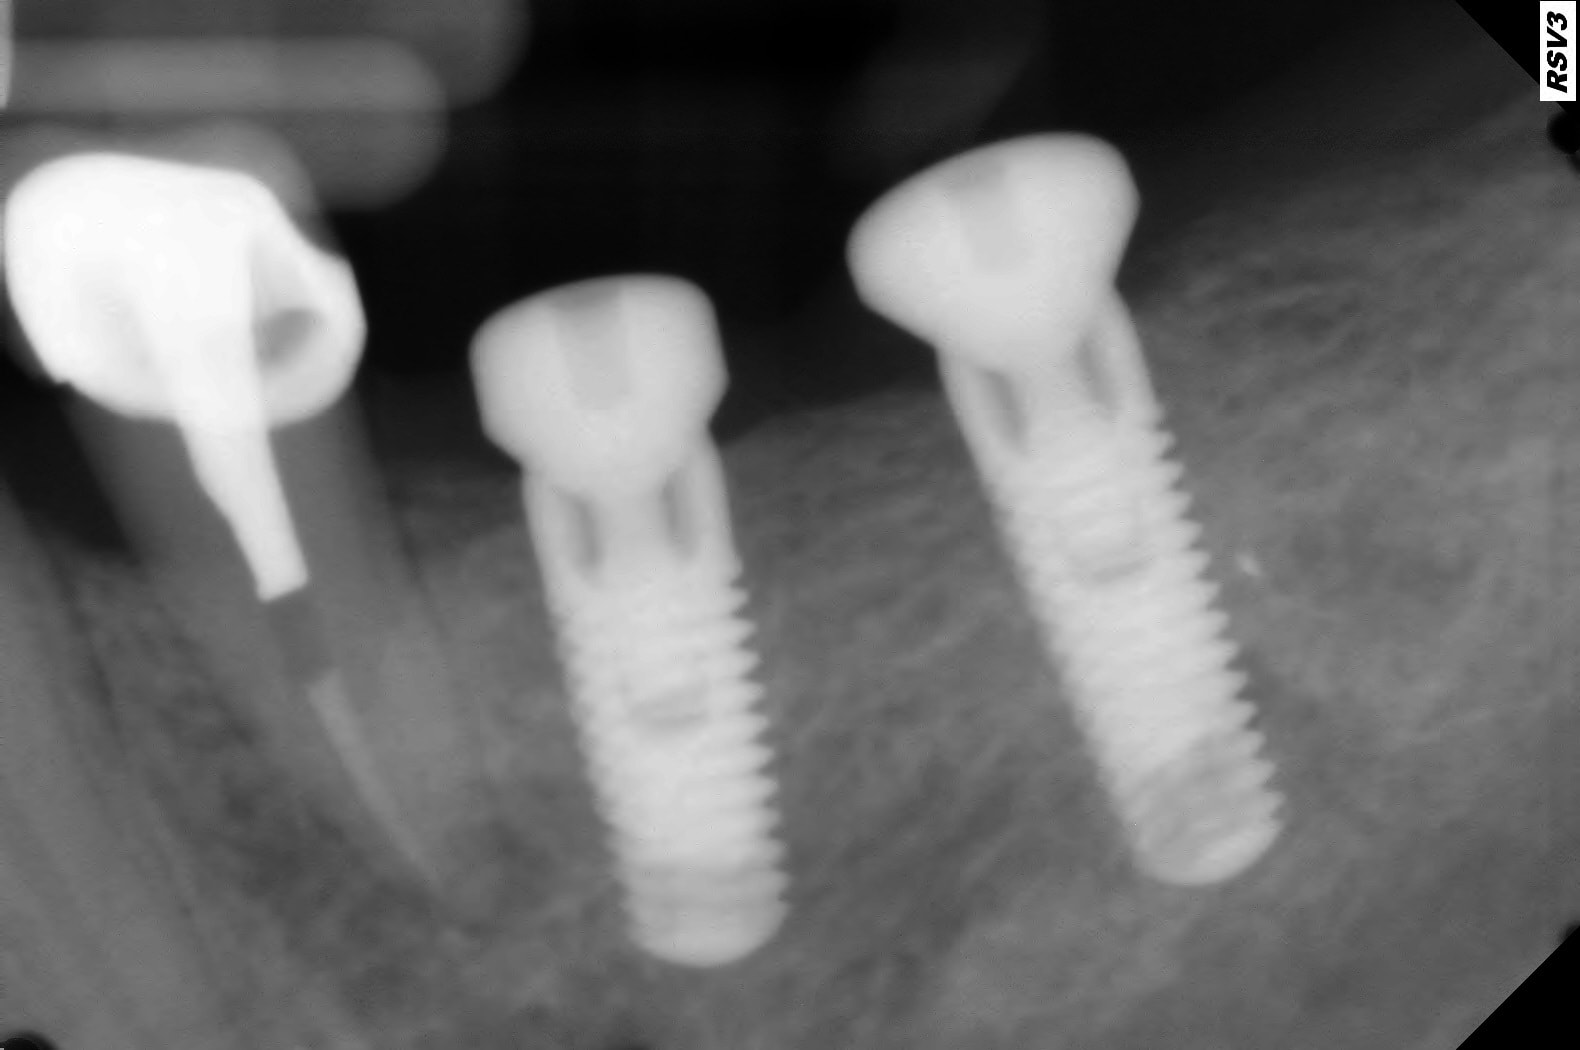

La qualité des radio avec capteur dépendent beaucoup du réglage du tube radio.

Par exemple avec mon tube satélec Xmind je suis à 0.10 sec avec 70kv et 8mA pour une rétroalvéolaire sur molaire maxillaire et un capteur RSV3 Visiodent .

Sur mon autre tube radio softy dental Wyndy avec un capteur kodak RVG5200 je suis à 0.20 sec avec 70kv et 8mA.

Il faut faire des tests.

Par contre le rendu avec des implants est différent en fonction des 2 capteurs . Je n'ai pas compris pourquoi.